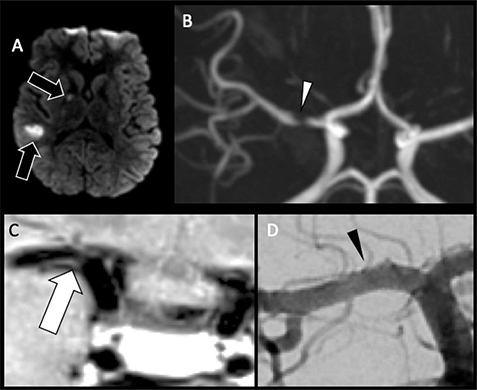

Focal cerebral arteriopathy (FCA), also known as transient cerebral arteriopathy, is a common cause of pediatric AIS in previously healthy children (Figure 1) (16, 17, 2124). Defined by an acute, monophasic illness causing unilateral stenosis of the intracranial cerebral arteries, mainly involving the anterior circulation, FCA was found in 36% of children presenting with acute stroke in one series (23). FCA can be further subdivided into the following subtypes: FCA– dissection type (FCA-d), FCA–inflammatory type (FCA-i), primary and secondary Moyamoya disease, genetic or syndromic arteriopathies (such as PHACE syndrome), vasculitis, fibromuscular dysplasia, and iatrogenic forms (Figures 2) (25, 26). The appropriate diagnosis is important to establish because prognosis can be improved by treatment of the inflammation, when present. FAC-i is associated with viral infection and vaccination may reduce the incidence (16, 17, 24, 27). Varicella zoster virus (VZV) is an established cause of FCA, although other pathogens, including other herpes viruses, likely play a role as FCA continues to occur in VZV vaccinated children (16, 28, 29). Age of onset differs between arteriopathy subtypes, with FCA-i tending to affect older school-aged children, Moyamoya affecting younger children, and dissection generally presenting no age predilection (30). COVID-19 has been reported as a cause of FCA, also resulting stroke related to the prothrombotic effects leading to AIS and venous sinus thrombosis (3133). Inherited vasculopathies include, such as mutation in ACTA2, with distinctive imaging features which may suggest such diagnoses (34). Disorders of coagulation may be identified, including deficiencies of proteins C and S, G20210A prothrombin mutations, and factor V Leiden, as well as the presence of anticardiolipin antibodies (19, 3538). In patients with no underlying metabolic disorders, trauma and previous viral infection are significantly more common (16, 17, 39, 40). Genetic or acquired conditions causing thrombophilia are less common causes (41).

Fig 1

Figure 1. A six-month-old male who presented with acute right hemiparesis. DWI (A) demonstrates acute infarct in the left basal ganglia and deep white matter (white arrow). MRA (B) shows severe stenosis of the left M1 middle cerebral artery segment (black arrow). Follow-up 4 months later, demonstrates evolution of the infarct, now with encephalomalacia and gliosis without new acute infarct (white arrowhead) (C). MRA at that times shows mild improvement but persistent MCA stenosis (black arrowhead) (D). Findings are most compatible with focal cerebral arteriopathy.